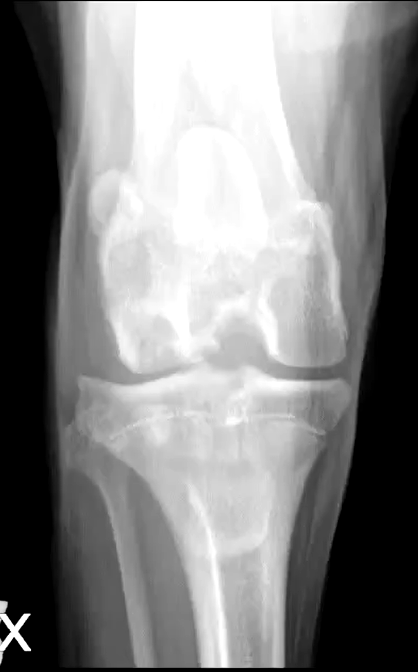

What are the radiographic findings of osteochondrosis in the stife?

Flattening or subchondral defect

Subchondral sclerosis

Detached mineralized cartilage flap

DJD

Osteochondrosis